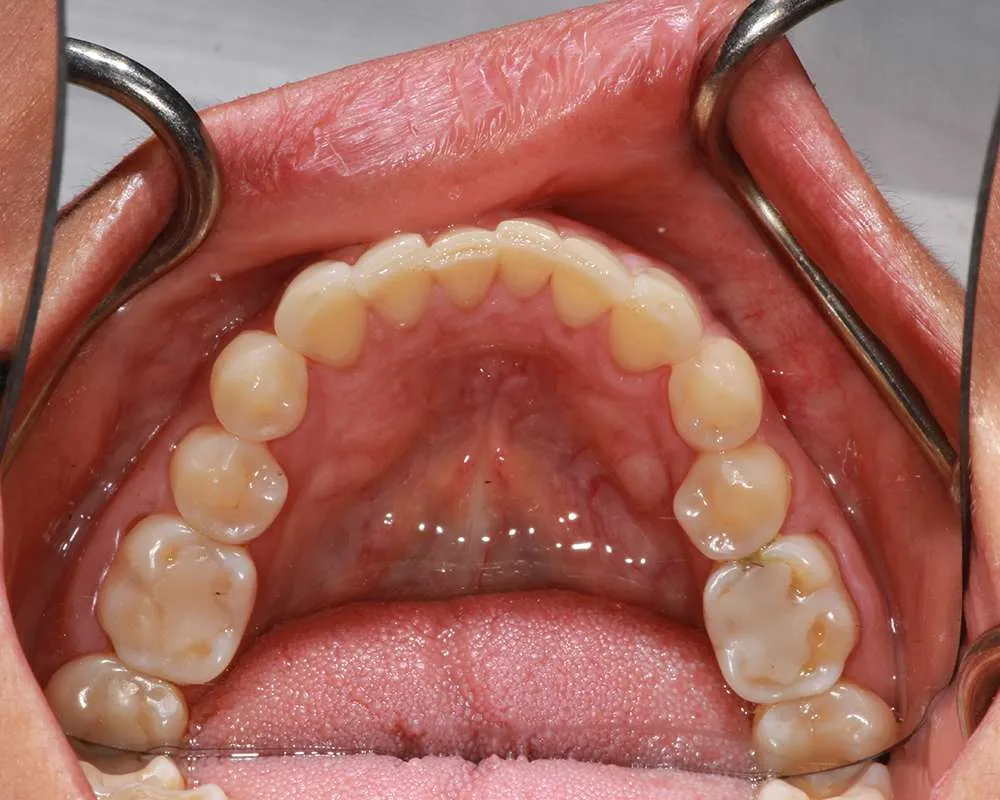

Real Stories, Real Results: Case Studies Showcasing How Our Personalized Approach Transforms Smiles and Lives

Complex Cases

Witness the Remarkable Changes We Can Achieve